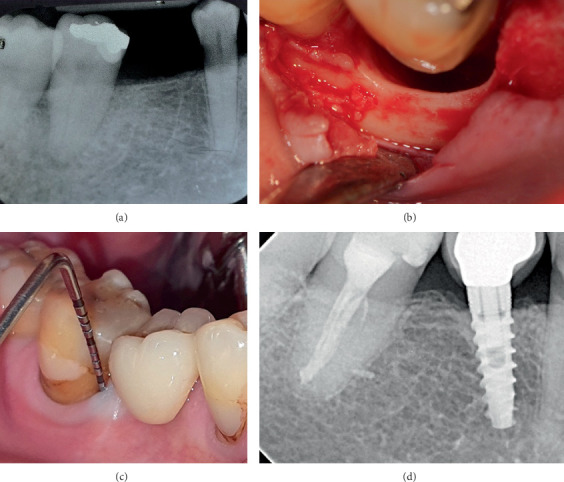

牙周再生(PR)可能是严重受损牙齿的一种可行的治疗选择。本病例系列通过长达13年的随访显示PR的长期益处。5例患者共6颗牙采用PR治疗骨内缺损。治疗方法包括提升粘骨膜瓣,根内固定,并用骨替代物填充骨缺损。PR后,探查深度(PD)明显减少(平均9.5±1.87 mm;p = 0.03),临床附着水平(CAL)也有统计学意义的增加(平均8.33±1.03 mm;P = 0.03)。x线片也证实了缺损部位骨缺损填充(平均9.67±2.25 mm;P = 0.03)。在长达13年的随访中,本病例系列表明,PR可减少PD,且牙龈萎缩最小,CAL增加,缺损部位骨填充,即使是复杂的牙周缺损延伸到根的根尖部分,这表明它是一种有效且可预测的治疗选择。

Periodontal regeneration (PR) could represent a viable treatment alternative for severely compromised teeth. This case series presents the long-term benefits of PR with up to 13 years of follow-up. A total of six teeth in five patients were treated for intrabony defects using PR. The treatment involved the elevation of a mucoperiosteal flap, root instrumentation, and filling the bony defect with bone substitutes. Following PR, a significant reduction in probing depth (PD) was observed (mean 9.5 ± 1.87 mm; p = 0.03) along with a statistically significant gain in clinical attachment level (CAL) (mean 8.33 ± 1.03 mm; p = 0.03). Radiographic bone defect fill at the defect site was also verified (mean 9.67 ± 2.25 mm; p = 0.03). This case series demonstrated that PR led to reduced PD with minimal gingival recession, gain in CAL, and bone fill at defect sites, even in complex periodontal defects extending to the apical portion of the root, over a follow-up period of up to 13 years, indicating it as an effective and predictable treatment alternative.